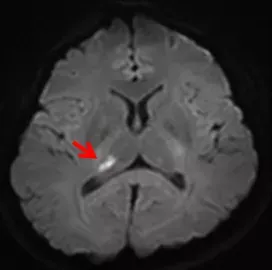

輕松的退休后生活卻被頭暈、昏沉反復打擾,哪里出問題了? 近期,鼓樓醫(yī)院江北國際醫(yī)院神經(jīng)內(nèi)科開展首例重度頸動脈狹窄球囊擴張并支架植入手術,重塑狹窄動脈形態(tài),顯著恢復腔內(nèi)血流,有效改善患者癥狀。 01 如此不適為哪般 老王今年60歲,剛辦理退休準備好好放松,但近兩年來一直受困于頭暈、頭昏,整天昏沉感、頭腦不清晰,尤其近兩周癥狀加重。老王就來到鼓樓醫(yī)院江北院區(qū)神經(jīng)科門診就診,醫(yī)生開具頭顱MRA檢查發(fā)現(xiàn),雙側額葉、頂葉多發(fā)亞急性梗死灶及陳舊性腔梗,并且右側頸內(nèi)動脈已經(jīng)閉塞了。于是,老王被安排住進A82病區(qū)神經(jīng)內(nèi)科病房。 02 規(guī)范檢查尋究竟 盡管老王的梗死病灶很小,卻呈現(xiàn)新舊交替、多發(fā)、雙側分布的特點。雖然沒有引起重要的神經(jīng)功能喪失,比如沒有肢體乏力、言語不清及口角歪斜等,但卻存在極大的安全隱患,如果不及時干預,未來發(fā)生中-重度腦梗死的風險非常高。 為此,神經(jīng)內(nèi)科邱樹衛(wèi)副主任醫(yī)師為老王制定了規(guī)范的診療計劃,以查明老王多發(fā)腦梗死與頸動脈閉塞的原因。結果陸續(xù)反饋:老王大部分抽血化驗正常,只有血脂-低密度脂蛋白膽固醇-是升高的;心臟彩超與動態(tài)心電圖是正常的,從而排除心源性病因;頭頸部CTA檢查發(fā)現(xiàn),老王的頸動脈狹窄遠比頭顱MRA所顯示的要嚴重的多,他的左側頸內(nèi)動脈同樣存在重度狹窄。 紅箭頭表示頸動脈開口處略呈擴張形態(tài),黃箭頭表示左側頸動脈重度狹窄,白箭頭表示右側頸動脈閉塞、狹窄。 經(jīng)過仔細梳理,老王有高血壓、糖尿病,常年沒有規(guī)律服藥,控制不佳,工作又忙于應酬,抽煙、飲酒,本次檢查發(fā)現(xiàn)血脂高,這些都是引起頸動脈粥樣硬化的危險因素,可謂“五毒俱全”,長此以往,導致頸動脈斑塊形成、狹窄、閉塞。老王的頭昏與視物模糊,是真正的腦供血不足癥狀。 03 藥物干預做配套 更要命的是,磁共振發(fā)現(xiàn)的新的點狀梗死灶,提示老王的頸動脈斑塊是“活動性”的,不穩(wěn)定的,不斷地有小斑塊脫落或微栓子形成,從而導致新舊交替形成的腦梗死。顯而易見,老王的頸動脈狹窄需要積極干預。 老王接受藥物強化治療,包括雙聯(lián)抗血小板聚集、強化他汀穩(wěn)定斑塊等,調(diào)控血壓、血糖。有癥狀的頸動脈顱外段重度狹窄患者,存在明確的血管內(nèi)治療指征,也就是所謂的支架治療。醫(yī)療團隊隨即向老王及家屬交代病情,充分告知腦血管造影及支架植入治療的安全性和有效性,老王表示充分信任鼓樓醫(yī)院的醫(yī)生與技術,欣然簽字同意手術。 04 重塑形態(tài)解頭暈 頸動脈成形及支架植入治療的目的是固定動脈斑塊,重塑血管形態(tài),從而恢復血管腔內(nèi)血流,鼓樓醫(yī)院神經(jīng)內(nèi)科已廣泛開展此項技術。伴隨著江北院區(qū)復合手術室條件的成熟,經(jīng)神經(jīng)內(nèi)科徐運主任統(tǒng)籌安排,老王將無需跨江輾轉(zhuǎn)即能接受最佳的支架治療。介入組負責人李敬偉主任專程到江北院區(qū)與老王進行二次術前談話,并與院區(qū)醫(yī)療團隊進行了密切對接。 手術當日,邱樹衛(wèi)副主任醫(yī)師與端光鑫醫(yī)生首先進行腦血管造影檢查,證實左側頸內(nèi)動脈與頸外動脈開口處嚴重狹窄,頗有一線天的既視感(視頻1),有明確支架治療指征。隨后李敬偉主任醫(yī)師親自主“刀”,采用球囊對狹窄處進行快、穩(wěn)、準的擴張,達到滿意程度后,再植入支架一枚,隨即復查造影顯示,狹窄處腔內(nèi)血流恢復(視頻2)?;氐讲》?,老王沒有任何不良反應,他非常高興,“現(xiàn)在頭腦終于恢復清清爽爽的感覺,眼睛也明亮了(血供增加的緣故)。” 視頻1 視頻2 本文發(fā)表于南京鼓樓醫(yī)院江北國際醫(yī)院公眾號,作者:邱樹衛(wèi)。 https://mp.weixin.qq.com/s/QcZJx1V1wb2af65W_I1QPg